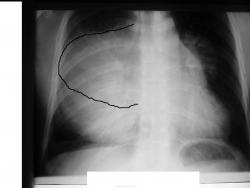

Мужчина 36 лет, рентгеногафия и КТ грудной полости.

Жалобы на субфебрильную температуру, боли в грудной клетке справа, слабость, похудание. ФГ 10 месяцев назад - норма.

Выглядел R-снимок 14.07.09 примерно так

Интенсивное, однородное затемнение в средних отделах справа, слева норма - мною был заподозрен м/долевой плеврит, пациент был направлен в областной центр торакальной хирургии. Затем онкодиспансер, затем институт рака в Киеве. Результат гистологии тератобластома средостения. 2 курса химиотерапии контрольное КТ в октябре - отрицательная динамика.